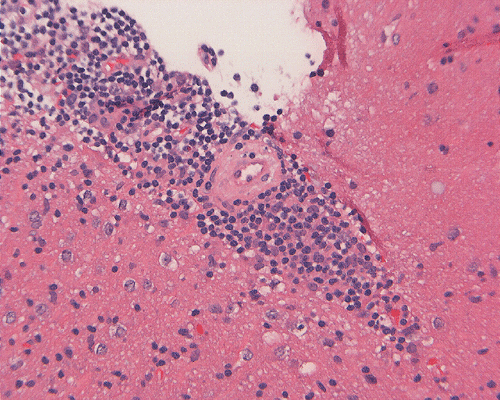

Microscopically, the morphology is similar to the corresponding type of lymphoma that occurs in other parts of the body. The neoplastic cells demonstrate a classic perivascular infiltration that dissects the perivascular reticulin network. Geographic necrosis may be seen when tumors become confluent, with perivascular islands of viable tumor cells surrounded by large regions of coagulative necrosis. As most of the PCNSL are of diffuse large B-cell type, the neoplastic cells are typically highly pleomorphic and large. Low-grade lymphomas are relatively uncommon.

Their immunohistochemical profiles are similar to lymphomas that occur outside the central nervous system. Intraoperative recognition of an atypical lymphoproiferative lesion is important as fresh tissue can be sent for flow cytometry which is often an important adjunct for correct diagnosis.